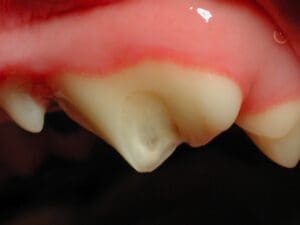

A fractured lower canine tooth in a dog. The dark, central part is exposed pulp canal

Fractured teeth hurt and become infected . The tooth is comprised of three main layers: the outer enamel, the middle dentin, and the inner pulp. The pulp contains living tissue made up of arteries, veins, lymphatics, connective tissues, and nerves. This is where the sensory pain receptors are located. The pulp, when exposed, may appear pink or black (as seen above).